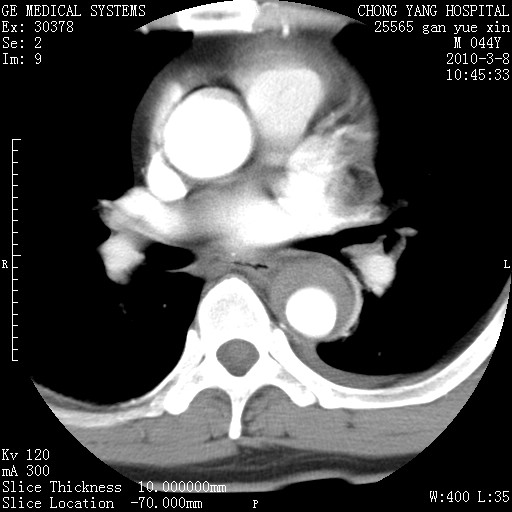

标题: CT24940:主动脉增强,典型病例。 [打印本页]

标题: CT24940:主动脉增强,典型病例。

夹层动脉瘤。

动脉夹层

夹层动脉瘤,典型

主动脉夹层。

动脉夹层的分型:

⒈debakey分型:根据主动脉夹层累及部位,分为三型:ⅰ型:原发破口位于升主动脉或主动脉弓部,夹层累及升主动脉、主动脉弓部、胸主动脉、腹主动脉大部或全部,少数可累及髂动脉。ⅱ型:原发破口位于升主动脉,夹层累及升主动脉,少数可累及部分主动脉弓。ⅲ型:原发破口位于左锁骨下动脉开口远端,根据夹层累及范围又分为ⅲa,ⅲb。ⅲa型:夹层累及胸主动脉。ⅲb型:夹层累及升主动脉、腹主动脉大部或全部。少数可累及髂动脉。

⒉stanford分型:a型:夹层累及升主动脉,无论远端范围如何。b型:夹层累及左锁骨下动脉开口以远的降主动脉。

夹层动脉瘤,少量胸水

夹层动脉瘤;左侧少量胸腔积液。

典型主动脉夹层。